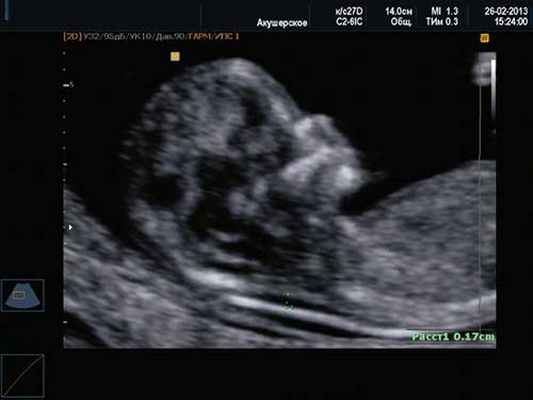

1. Ниже на УЗИ мы видим нормальную носовую кость. Можно различить 3 четкие линии.

2. Гипоплазия носовой кости. УЗИ сделано на 12 неделе беременности. Длина — 1,4 мм (ниже границы нормы).